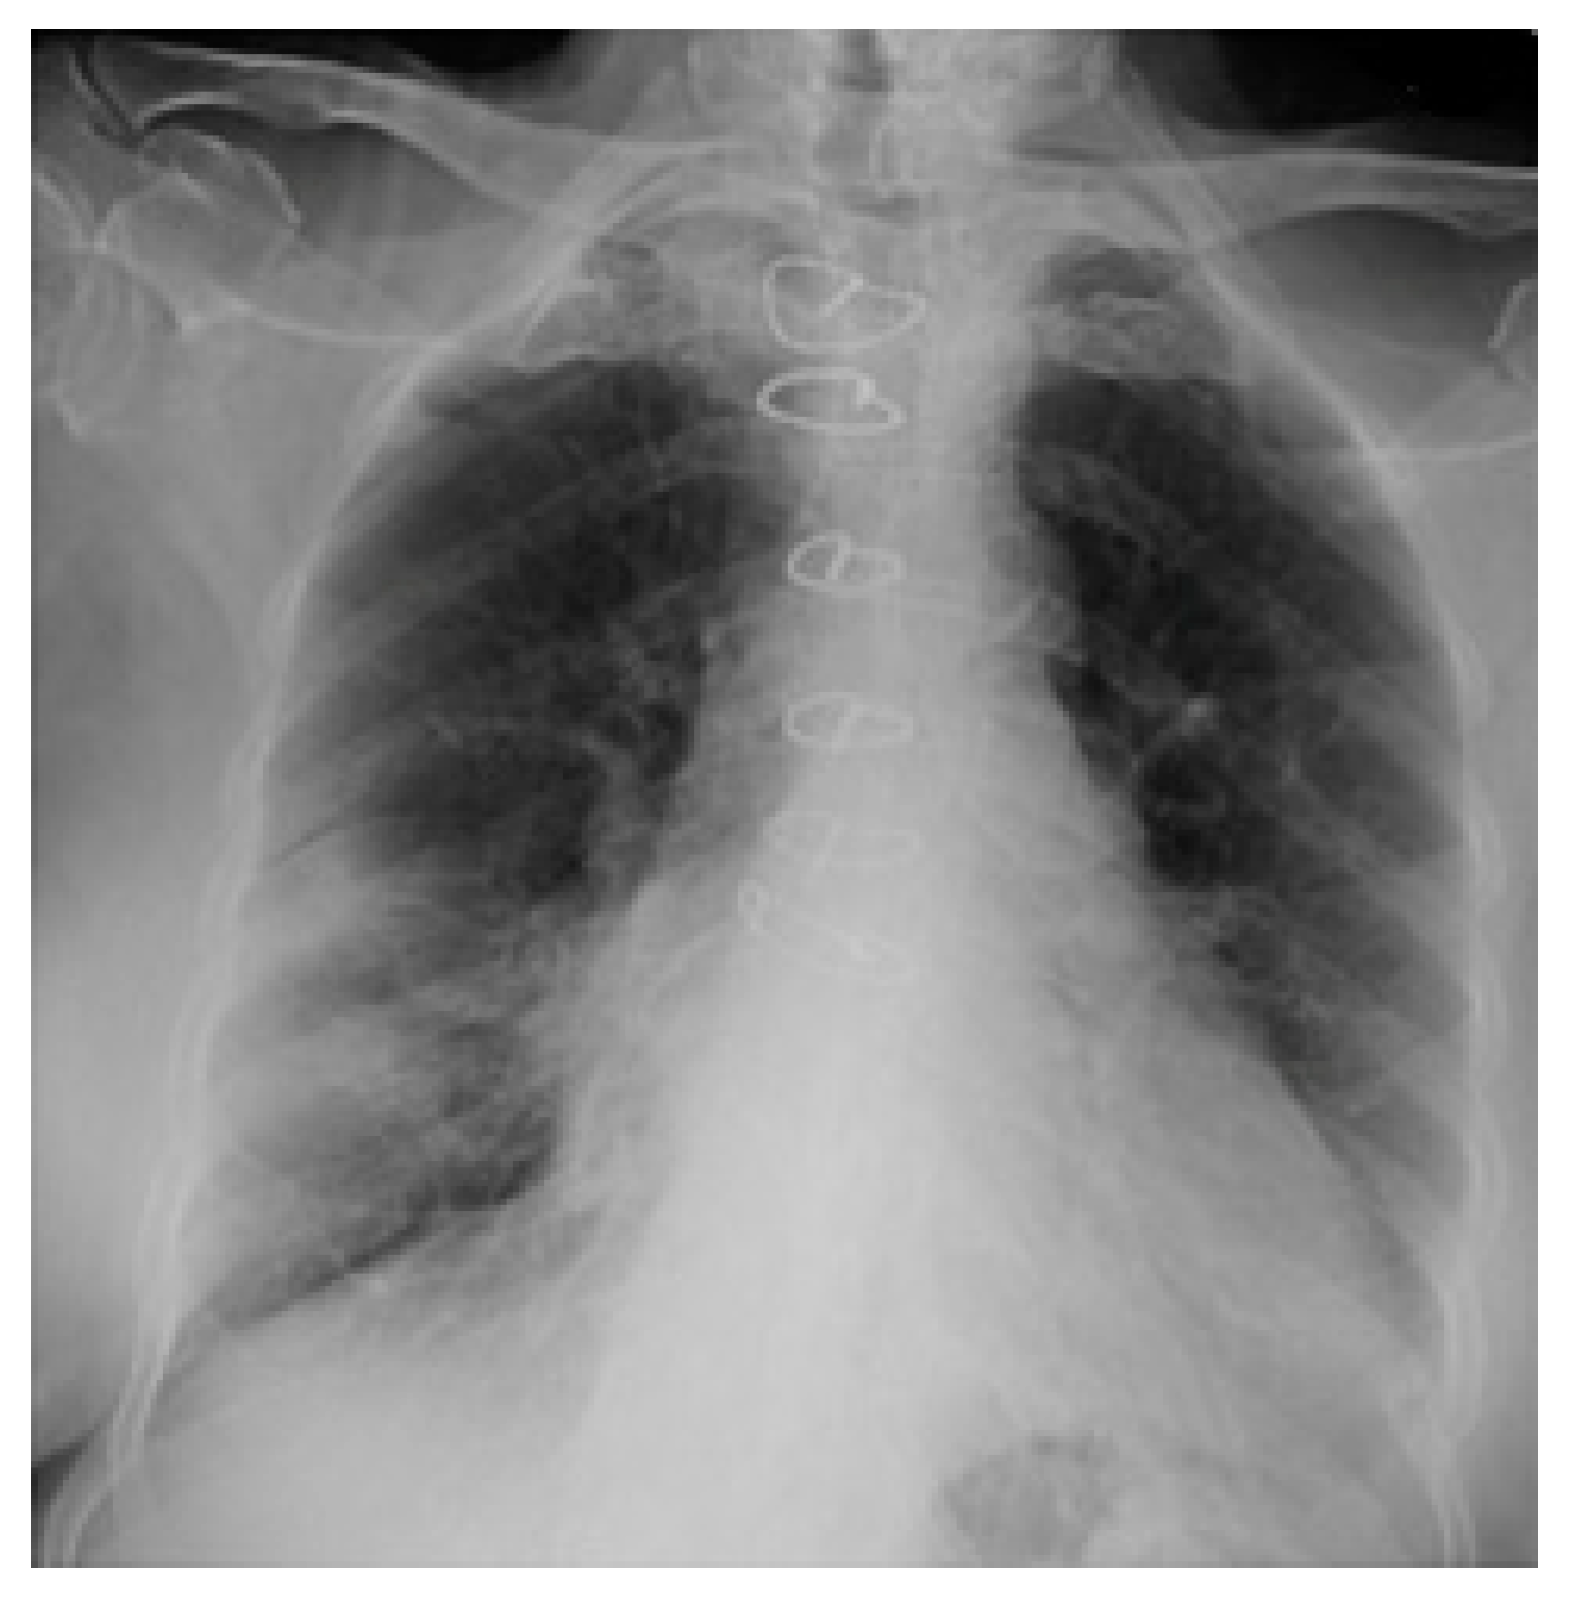

2.3. Imaging and Analysis